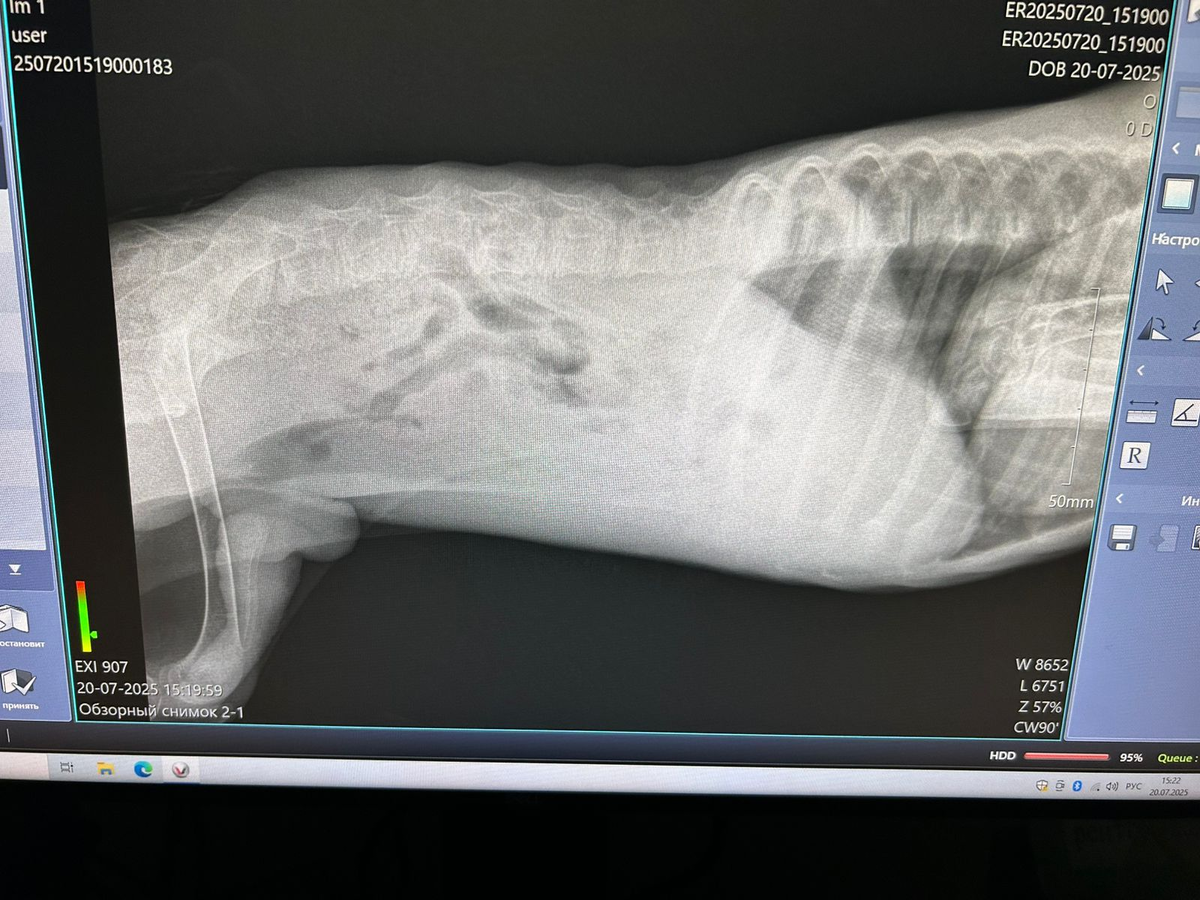

Дмитрий Викторович осмотрел, договорились, что будем орган спасать🙏🏻, как то ушивать, на всякий случай попросила сделать рентген, он сказал кости совсем прозрачные, у щенка кроме перелома в области таза, ещё и вторичный алиментарный гиперпаратериоз, другими словами, рахит, чувствительности так и нет, всё таки, спинальник, как и говорил врач при самом первом осмотре в клинике Альфавет.

Осмотр малыша Лелика в клинике Айболит перед операцией.